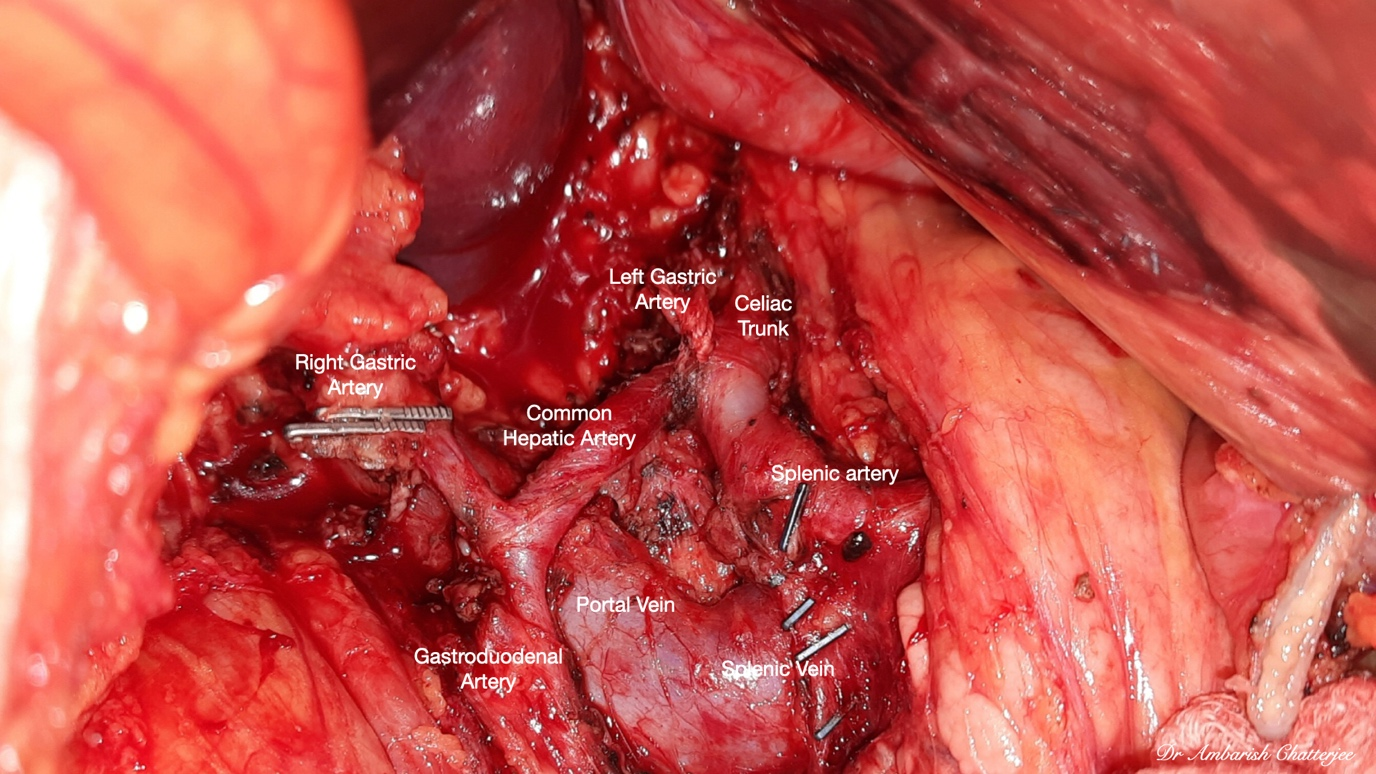

50 years old gentleman, diagnosed with gastric adenocarcinoma with gastric outlet obstruction. On CT scan the disease was localized to distal part of stomach. The patient underwent upfront laparoscopic subtotal gastrectomy with D2 lymphadenectomy and extracorporeal gastro-jejunal anastomosis. The intra-operative and post-operative period was uneventful. The patient was discharged on 7th post-operative day.